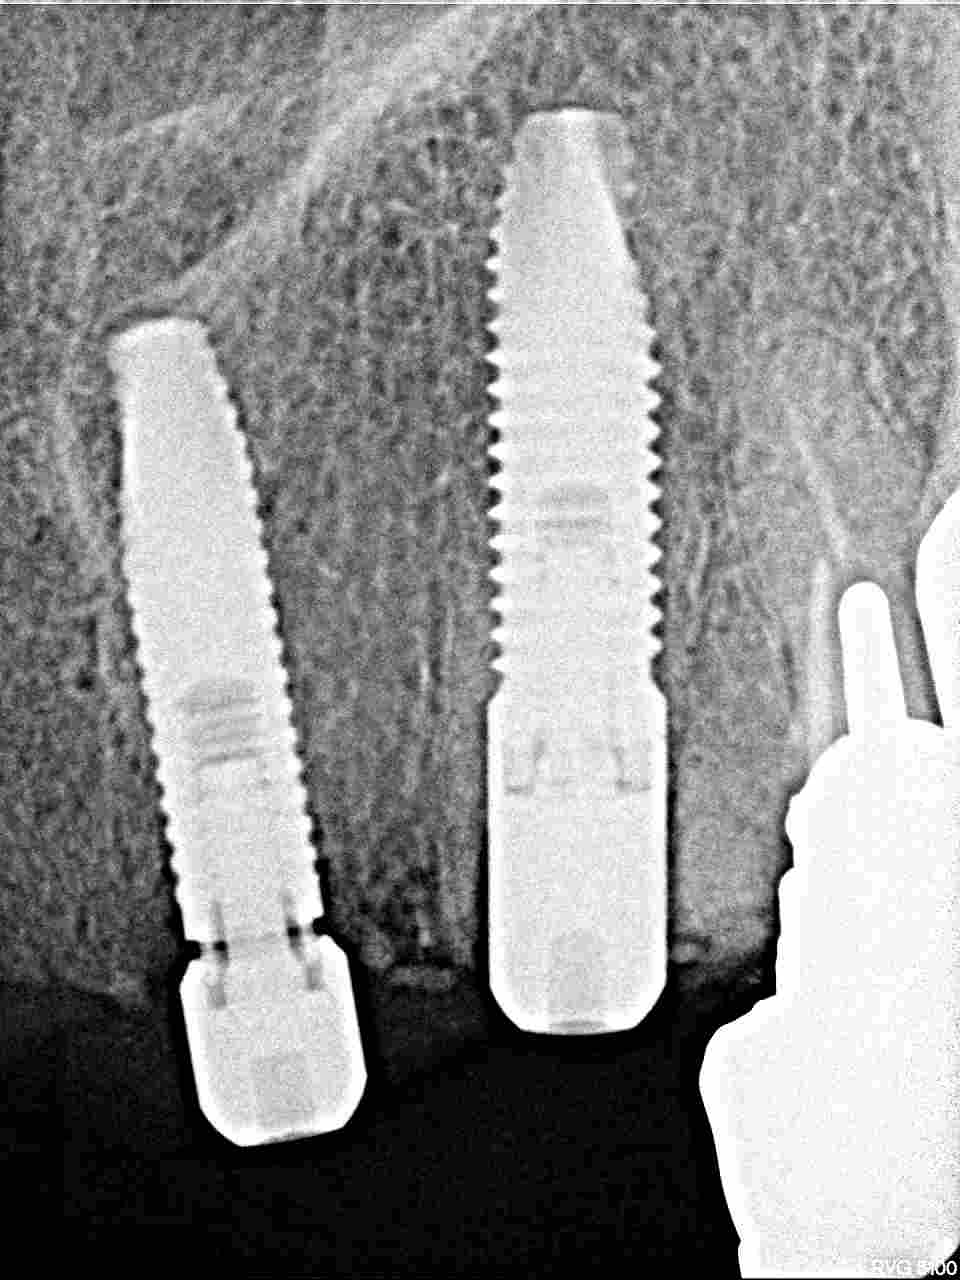

右上は大きく顎堤が無くなっていました

かなりの吸収量です

大きな吸収量です

2番は3.25mmの13mmというインプラントを埋入しています

3番は4,0mmの13mmというインプラントを埋入しています

術前のパノラマになります